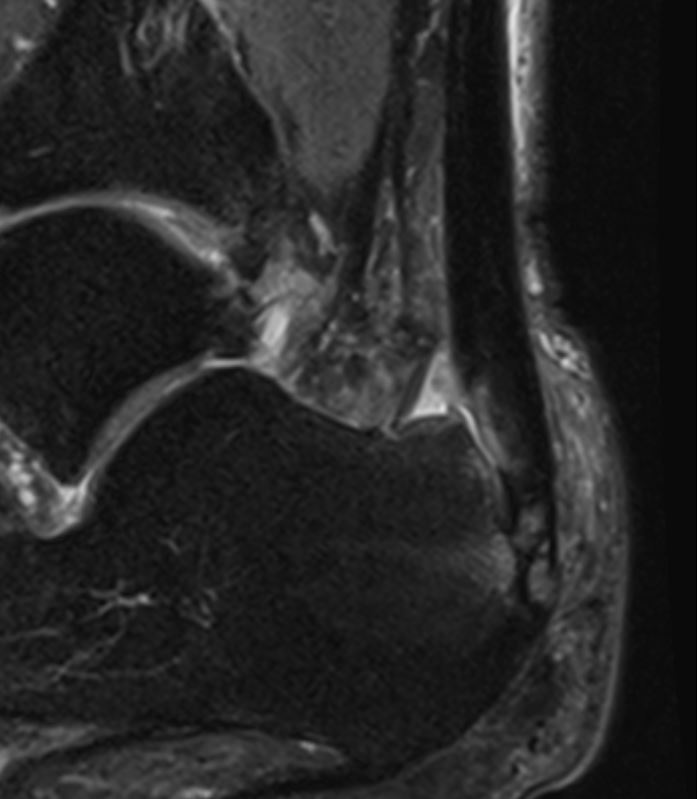

Haglund Syndrom und Bursitis subachillae 2020